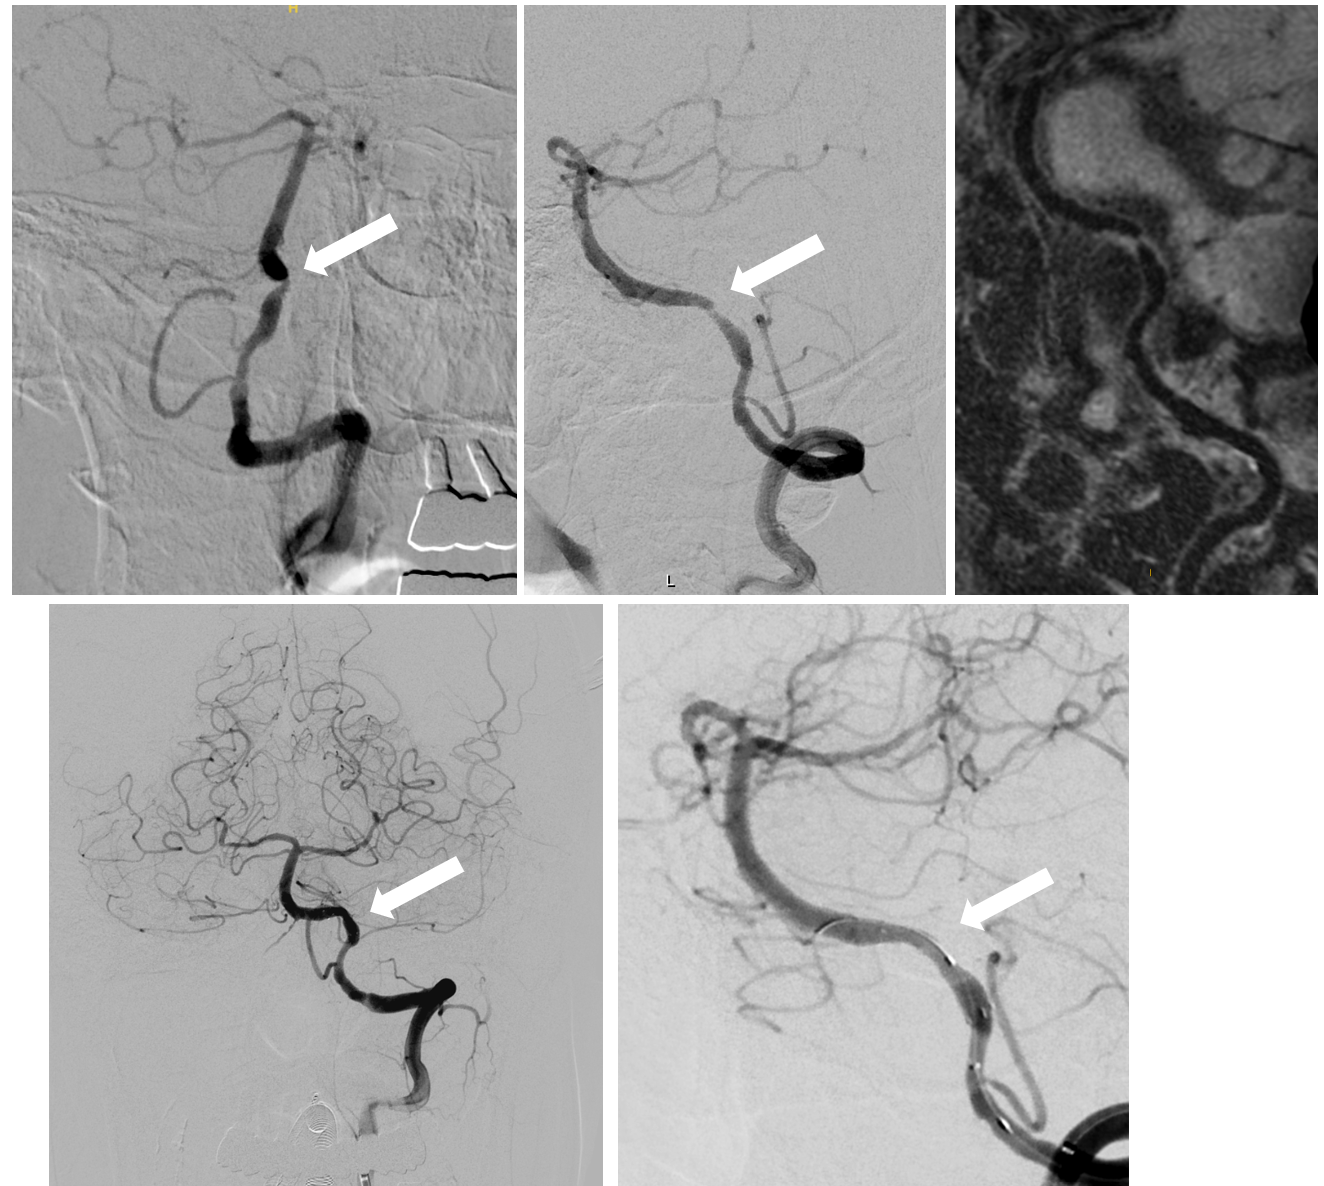

如图可见左侧半球患者脑梗死部位,左侧半球低灌注,左侧大脑中对面极重度狭窄,病变处为长节段斑块。术后通过支架治疗脑血管完全恢复。

对于脑梗死患者而言,如果在采取最优化药物治疗后,仍存在梗死风险,全麻下的支架治疗则成为了一种有效的治疗选择。特别是对于极重度狭窄病变,手术难度更是呈几何倍数增加。在这类手术中,医生首先需要在复杂的血管结构中寻找真实管腔,这犹如在迷宫中寻找出口,需要医生具备丰富的经验和敏锐的观察力。找到管腔后,再小心翼翼地进行球囊扩张,开辟出一条通道,这个过程就像是在薄冰上行走,稍有不慎就会引发严重后果。只有在通道成功开辟后,才能植入支架,打开血液流通的“隧道”。整个过程是在亚毫米级的精度下进行的,每一个操作都需要术者具备成熟的操作技术和冷静的判断能力,任何一个微小的失误都可能导致手术失败,给患者带来不可挽回的损失。